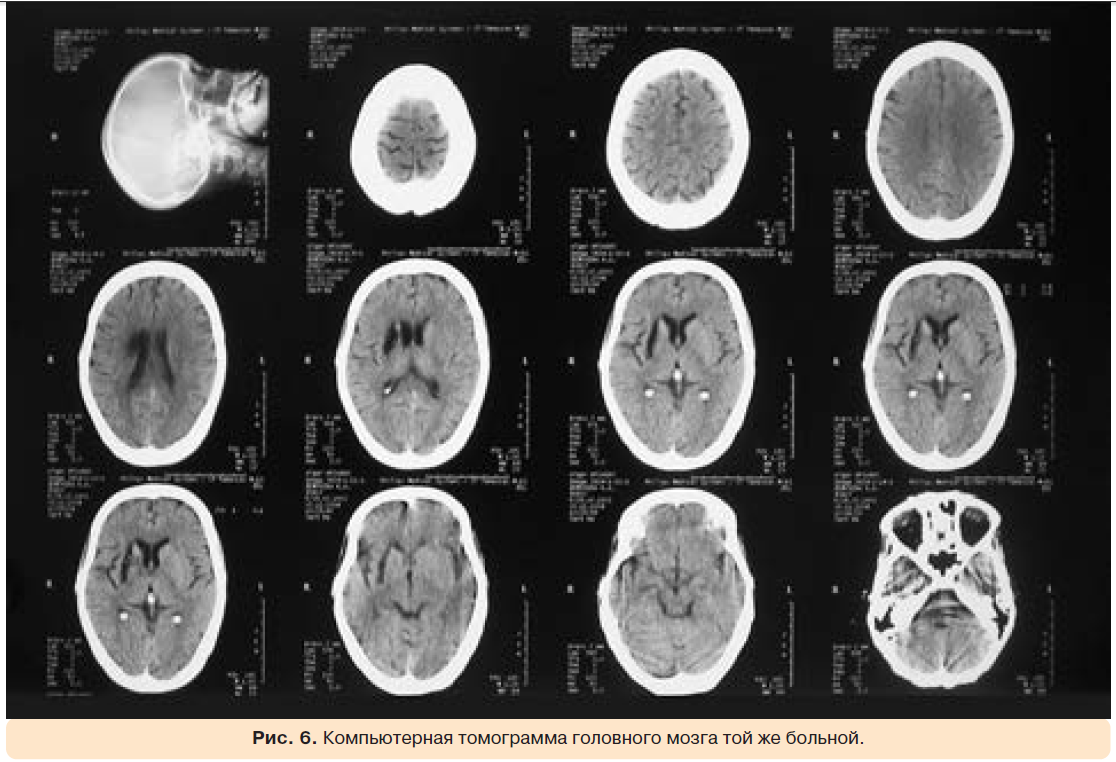

На рентгенограмме органов грудной клетки отмечались признаки застоя в малом круге кровообращения, жидкость в правой плевральной полости, границы сердца не расширены (рис. 5). За несколько месяцев до госпитализации у больной был эпизод дезориентации, сопровождавшийся психотическими нарушениями. В течение нескольких недель симптоматика регрессировала. При компьютерной томографии головного мозга была обнаружена киста в правой гемисфере: в медиальных отделах правой височной области, в проекции скорлупы, определялась зона низкой плотности (1–4 ед. Н) овальной формы, размерами 38×10 мм, с четкими, ровными контурами (рис. 6).